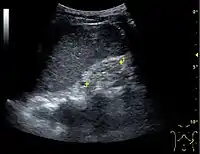

Figure 18. Renal stone located at the pyeloureteric junction with accompanying hydronephrosis.[1]

With US, larger stones (>5–7 mm) within the kidney, i.e., in the calyces, the pelvis and the pyeloureteric junction, can be differentiated, especially in the cases with accompanying hydronephrosis (Figure 18 and Figure 19). Hyperechoic stones are seen with accompanying posterior shadowing. Additional twinkling artifacts below the stone can often be seen using Doppler US. Large stones filling the entire collecting system are called coral stones or staghorn calculi and are easily visualized with US (Figure 20). Stones in the ureters are usually not visualized with US due to the air-filled intestines obscuring the insonation window. However, ureteral stones near the ostium can be visualized with a scan position over the bladder. An exam of the ureteric orifices and the excretion of urine to the bladder can be performed by inspecting the ureteric jets in the bladder with color Doppler US.